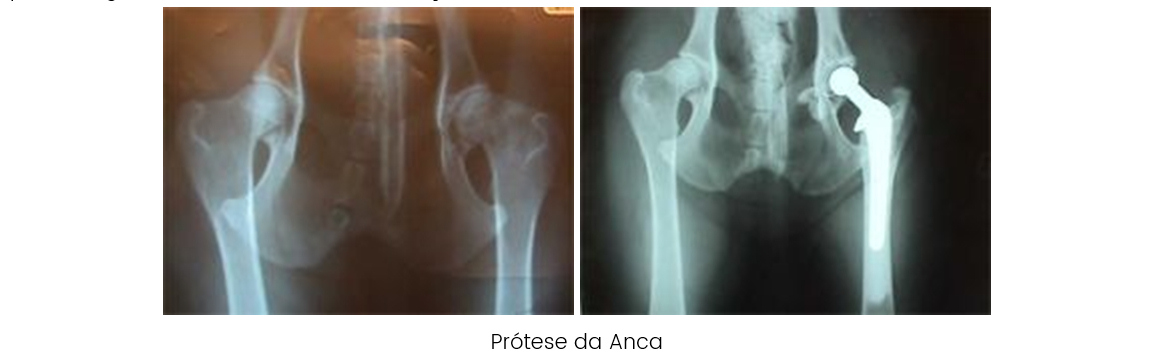

OSTEOTOMIA TRIPLA A osteotomia tripla do púbis, ísquion e ilíon,

liberta a parte acetabular, de forma a que se pode reorientar,

conseguindo uma maior congruência da mesma com a cabeça femoral,

diminuindo assim, a laxidão da cápsula articular, e evitarmos as

lesões degenerativas da articulação. O candidato ideal para uma

osteotomia tripla é um animal com displasia acetabular de 7 a 12

meses de idade com laxidão articular que clinicamente manifeste

sintomatologia e que não apresente sinais de degeneração

articular. Podemos rodar o acetábulo 20, 30 ou 40º.

O Hospital Veterinário do Porto com uma equipa cirúrgica

chefiada pelo Dr. Mário Santos, tem vindo ao longo de 4 anos, a

realizar as osteotomias triplas em muitos animais afetados, por

esta doença de todas as regiões do país. Cremos que é o melhor

método cirúrgico para corrigir a displasia, sendo a seleção dos

pacientes, assim como, a idade, de primordial importância para

que o êxito seja de 100%.

A rotação no caso acima descrito foi de 30 º, a radiografia foi efetuada após a cirurgia. Podemos verificar a introdução total da cabeça femoral no acetábulo no pós-cirúrgico. DARTROPLASTIA. É a cirurgia mais recente que utilizamos para corrigir a displasia em animais que já passaram os 12 meses de idade e que já não podem realizar uma osteotomia tripla. Contudo não são candidatos a uma cirurgia de prótese da anca ou muito menos a uma artroplastia por excisão. A cirurgia consiste em aumentar o acetábulo com uma técnica bastante eficaz e que mantém a cabeça do fémur estabilizada. Temos vindo a realizar esta técnica, desde há dois anos, conseguindo resultados extraordinários.

ARTROPLASTIA: A excisão da cabeça do fémur só deve ser utilizada como último recurso. O fim que perseguimos é a supressão da dor, eliminando a articulação. A recuperação funcional é mais lenta.

PRÓTESE TOTAL DA ANCA: A substituição da articulação coxo femoral em animais com osteoartrose por uma prótese é uma técnica cada vez mais utilizada. Geralmente utilizam-se próteses cimentadas com uma percentagem de êxito 60 a 100% em função da técnica utilizada.